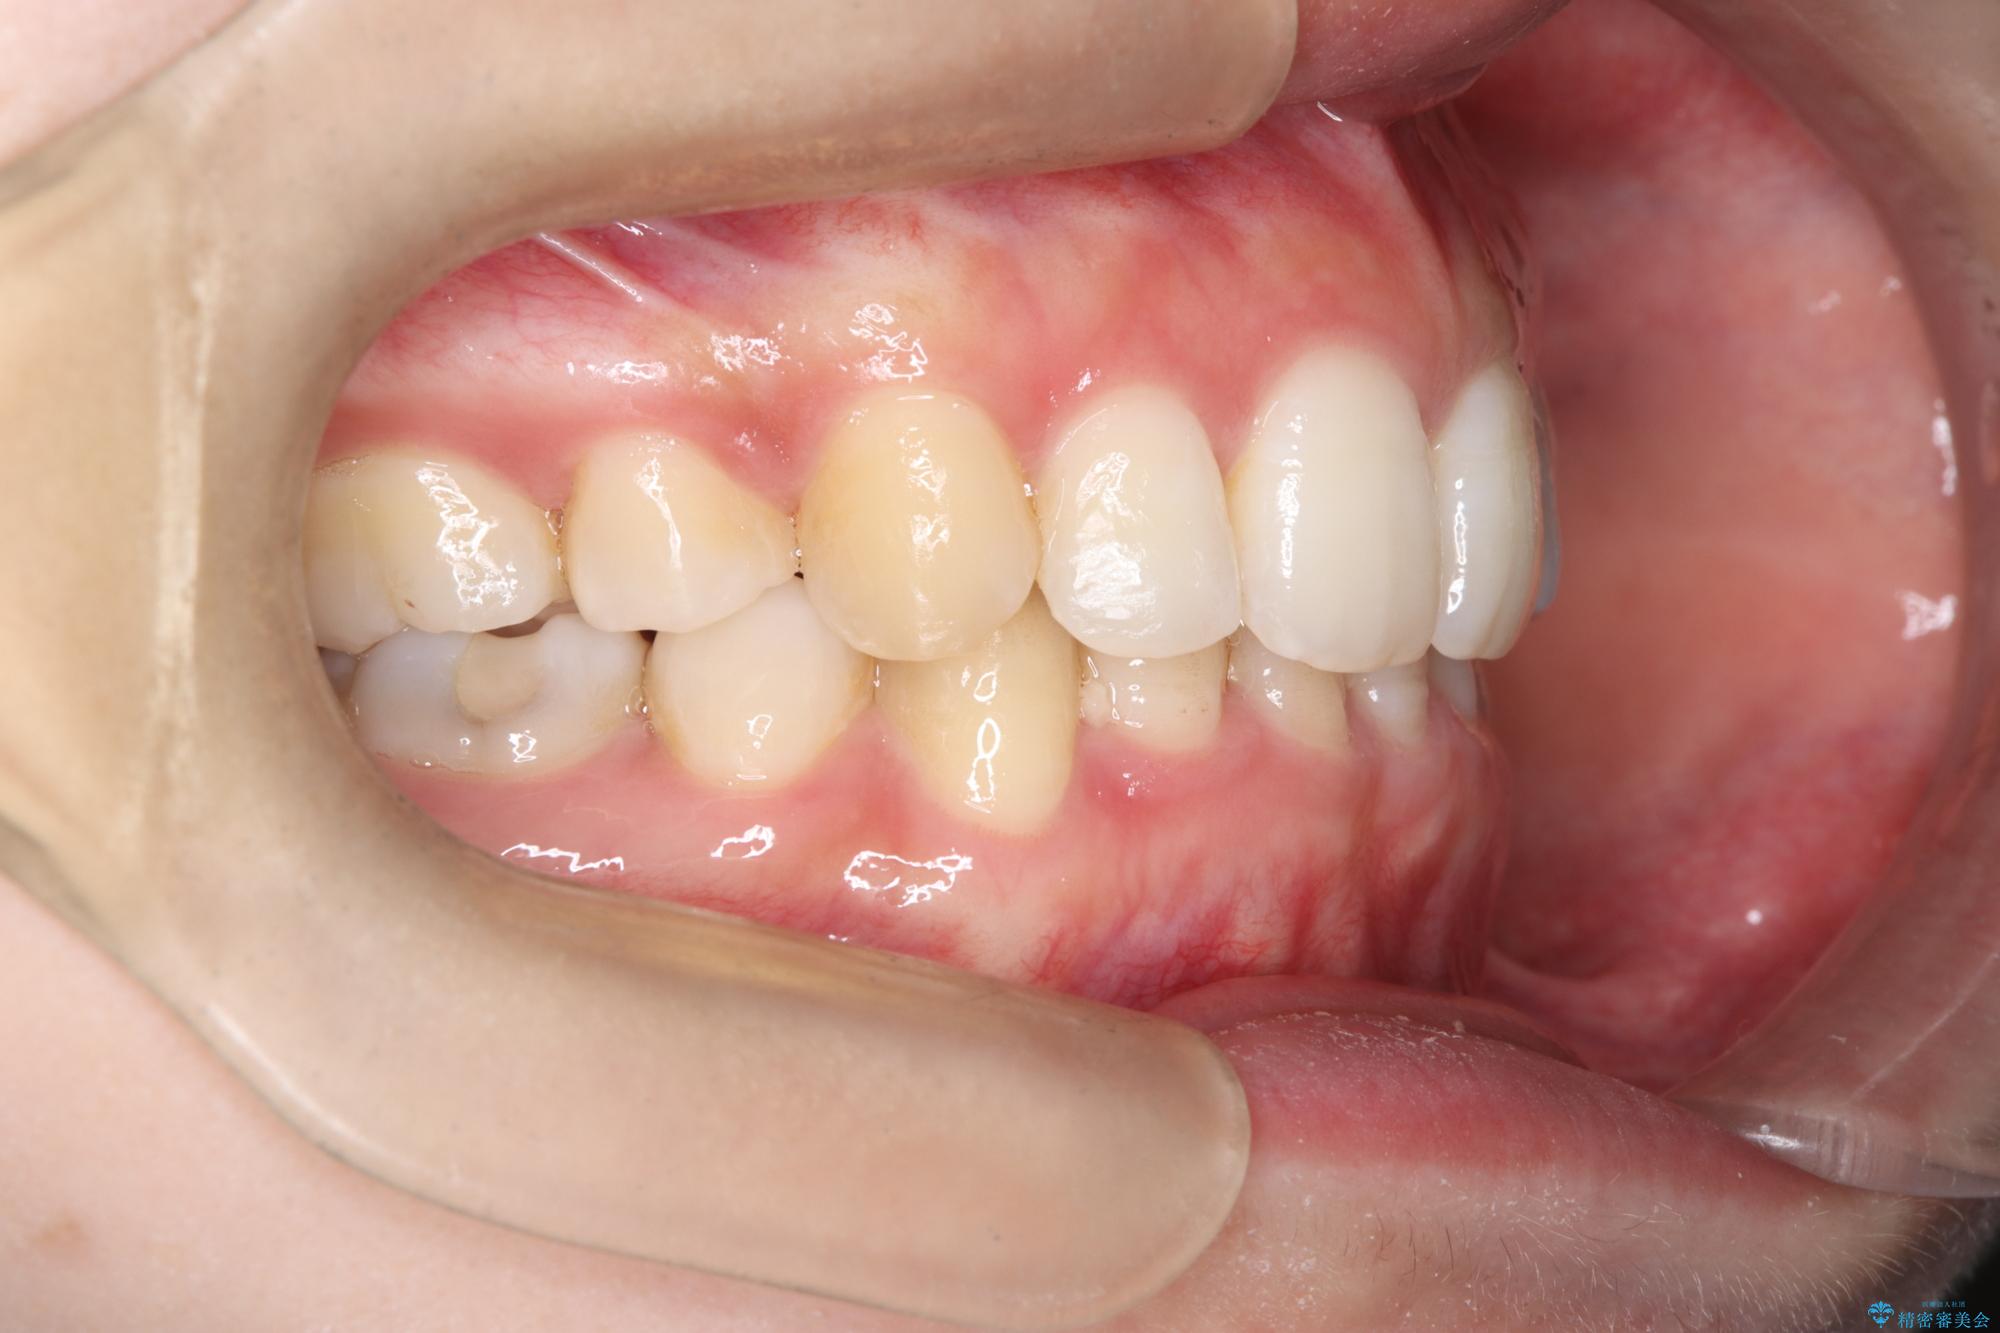

- 前歯から奥歯にかけて歯の重なりが激しい歯のがたつき(重度叢生)を主訴にご来院されました。精密検査の結果、歯が並ぶスペースが大幅に不足しており、歯並びを整え、口元を美しく引っ込めるためには、スペースの確保が必要と診断しました。そこで、上下左右の第一小臼歯(4番目の歯)を計4本抜歯し、そのスペースを利用して歯並び全体を整える抜歯矯正の治療計画を立案。装置には、透明で目立たないインビザラインを採用し、審美性と治療効果の両立を目指しました。

今回の治療では、重度の叢生を改善するため、まず計画通り上下左右4本の小臼歯を抜歯し、歯を並べるための十分なスペースを確保しました。装置には透明で取り外し可能なインビザラインを使用。抜歯によってできたスペースを最大限に活用し、マウスピースを定期的に交換しながら、デコボコを解消しつつ、前歯を効果的に後退させました。

治療の結果、長年の悩みであった重度の歯のがたつきが解消され、口元の突出感も改善。機能的にも安定し、審美的にも美しい、理想的な歯並びを獲得していただけました。